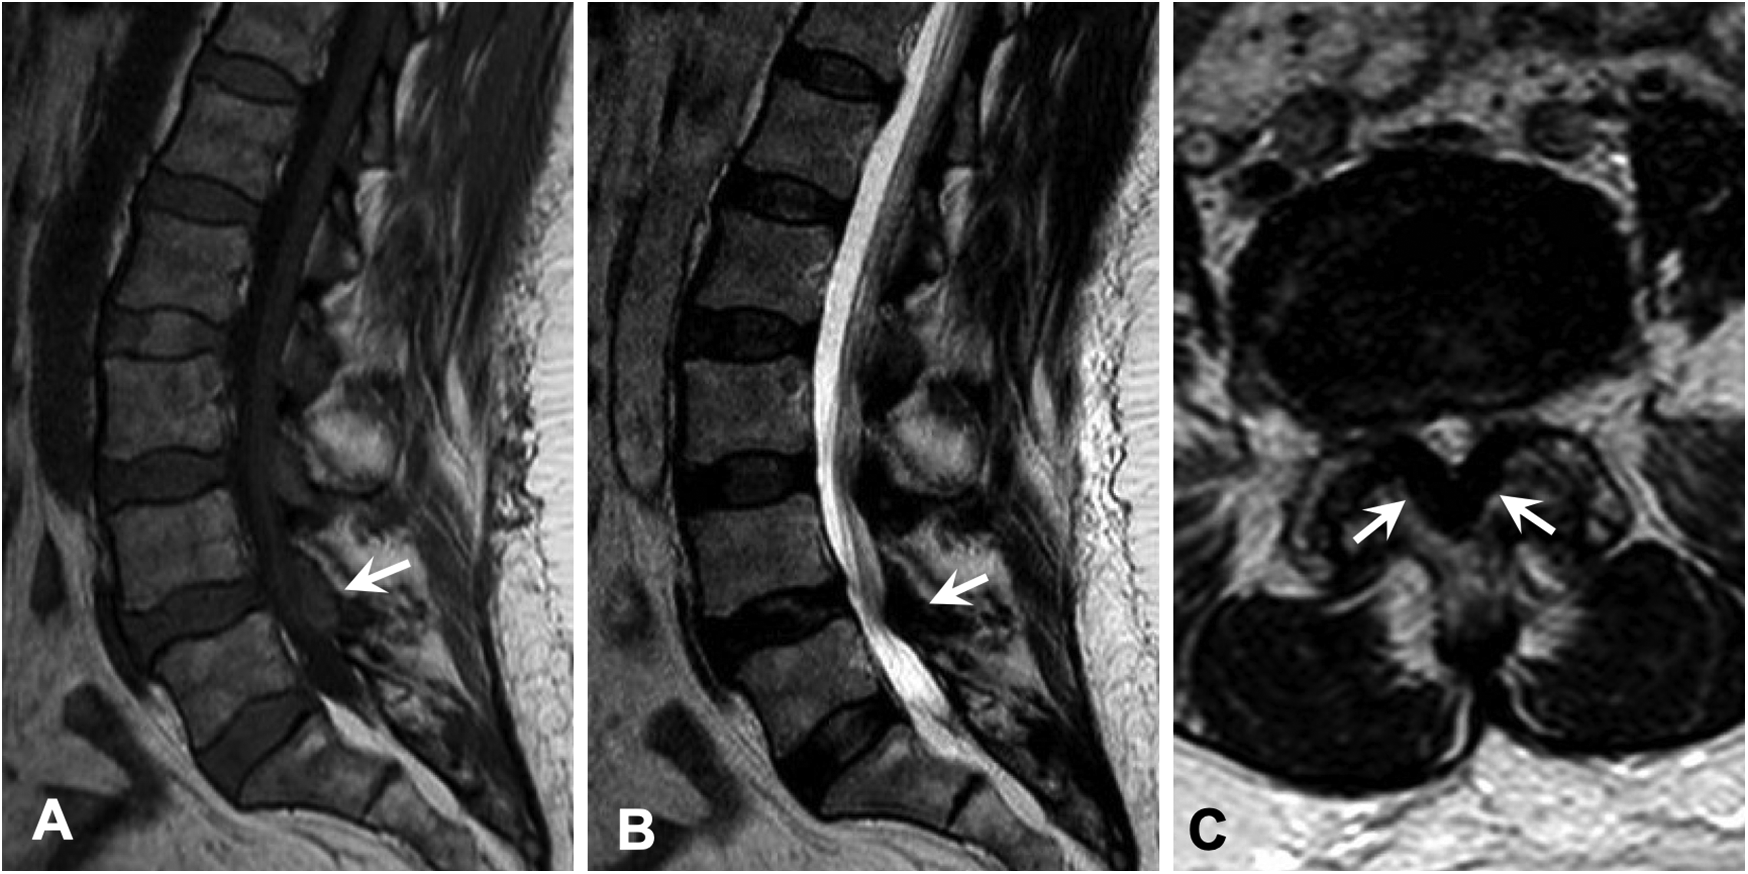

As for the lower back pain, magnetic resonance imaging (MRI) of the lumbar spine showed severe thickening of the ligamentum flavum (LF) at the level of L4–5 and severe narrowing of the spinal canal and bilateral neural foramina (Figures 2A–C). Given the sciatica symptoms refractory to physical therapy and pain medications, the patient underwent an L4–5 laminectomy and onlay arthrodesis, with subsequent relief of her back pain. The removed thickened LF was sent for biopsy and showed positive Congo red staining; LC/MS confirmed κ-type AL (Figures 1C,D) and the calculated amyloid load was 5.5% (Figure 3). The amyloid load was defined as the percentage of LF tissue occupied by amyloids and was quantified using a previously validated machine-learning model developed using Trainable Weka Segmentation (Fiji Version 2.1.0/1.53c) (6). The entire specimen displayed in Figure 3A was utilized for amyloid quantification.

Figure 2

Magnetic resonance imaging of the lumbar spine demonstrated severe thickening of the ligamentum flavum at the level of L4–5 (arrow) with associated abnormal T1 hyperintensity, which caused severe narrowing of the spinal canal and bilateral neural foramina. Similar lesions were also seen at the levels of L1–4 to a lesser extent. (A) Sagittal T1-weighted image. (B) Sagittal T2-weighted image. (C) Axial T2-weighted image.